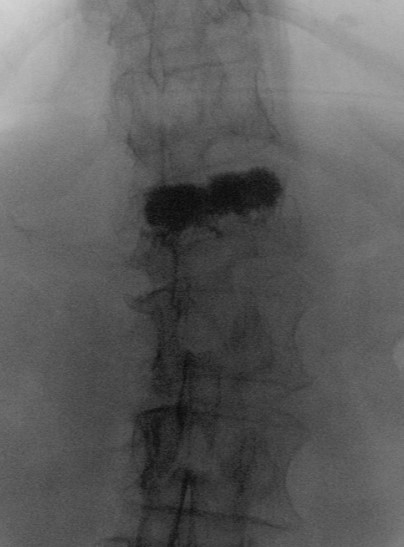

Vertebroplastie LWK1

A/P Röntgensicht einer Vertebroplastie auf Höhe LWK1